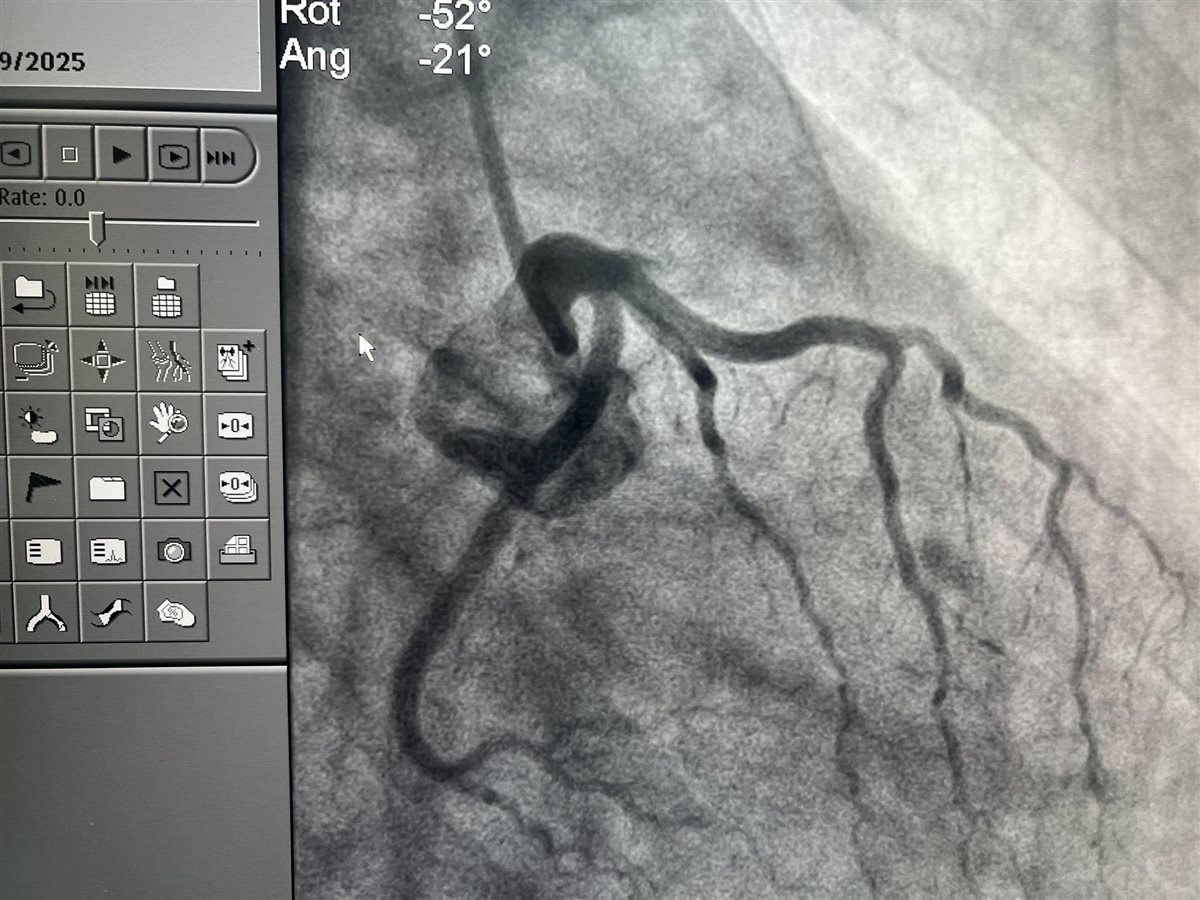

وقال في منشور له عبر حسابه على موقع التواصل الاجتماعي فيس بوك مرفقا بعدد من الصور للفحوصات الخطيرة للشباب: خلال ثلاثة أيام فقط من عيد الأضحى، استقبلنا بالمستشفى 13 حالة طوارئ مصابة بجلطات حادة في القلب، وجميعها من فئة الشباب الذين لا يعانون من أي أمراض مزمنة أو عوامل خطر تقليدية كارتفاع ضغط الدم أو مرض السكري، والعامل المشترك الوحيد بينهم كان تعاطي الحشيش.

وتابع حلمي راصدًا حجم المعاناة: كما استقبلنا شابًا يبلغ من العمر 28 عامًا، لا يعاني من أي أمراض مزمنة، لكنه أصيب بجلطة حادة بالقلب وكان الشريان التاجي في حالة سيئة جدًا لا تتناسب مع سنه، وفي حالة أخرى، شاب في الثانية والثلاثين من عمره خرج من مستشفى بعد فحص أولي طبيعي، لكن مع أول رسم قلب عندنا ظهر ارتفاع ST واضح، وتبين في القسطرة أن الشريان التاجي الأمامي النازل كان غير ظاهر تمامًا، وكدنا نظن أنه غير موجود، لكننا بفضل الله وبتعاون فريق القلب في المستشفى استطعنا تحديده وتوسيعه وتركيب دعامة لإنقاذ حياته.